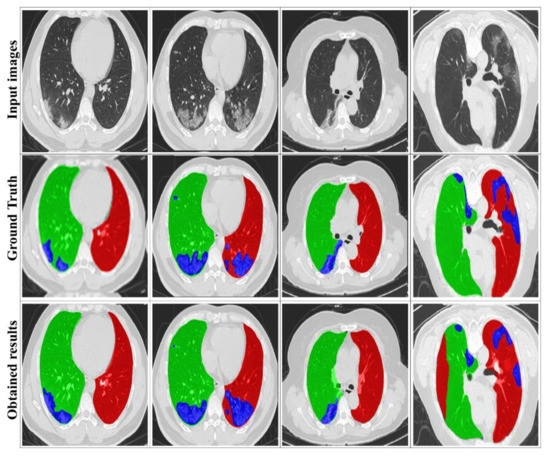

4.3. Evaluation of the DRL System

4.4. Comparison with State-of-the-Art Methods